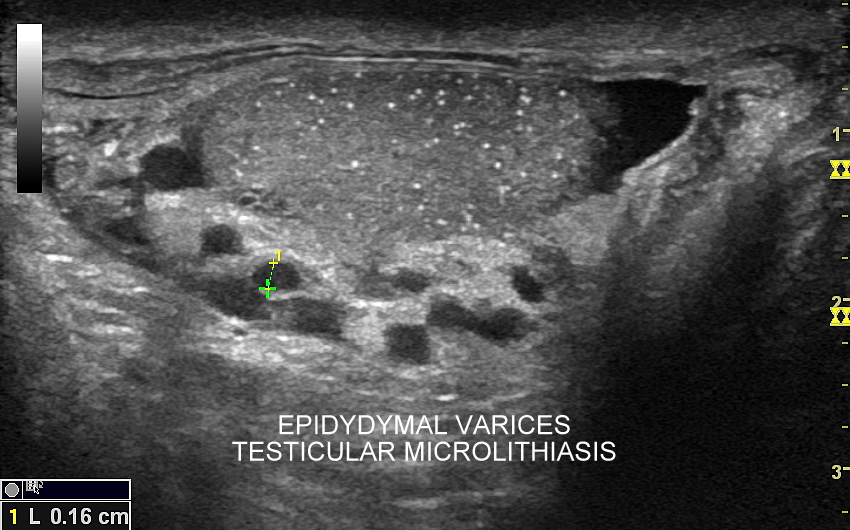

Najczęstsze choroby w obrębie moszny obejmują żylaki powrózka nasiennego, zapalenia jąder i najądrzy, wodniaki jądra, skręty szypuły jądra bądź przydatków jądra, torbiele najądrzy, nowotwory i raki jąder. Niezależnie od powyższego u chłopców spotyka się wnętrostwo, czyli niepełne zstąpienie jądra do moszny, które to może pozostać w jamie brzusznej lub pachwinie, a także ektopię jąder, czyli ich zabłąkane położenie (np. w okolicy krocza).

Mosznę bada się aparatem USG wyposażonym w dedykowaną sondę o wysokiej rozdzielczości przeznaczoną do oceny jąder i drobnych struktur moszny, koniecznie z zastosowaniem trybów dopplerowskich, takich jak Doppler kodowany kolorem, Doppler spektralny i obrazowanie mikrounaczynienia. Dopełnieniem badania USG jąder jest użycie w stosownych przypadkach trybu elastografii oraz trybu USG z kontrastem (CEUS). Lekarzem, który pierwszy we Wrocławiu i na Dolnym Śląsku przeprowadził badanie CEUS jąder jest dr Tomasz Szczepański.